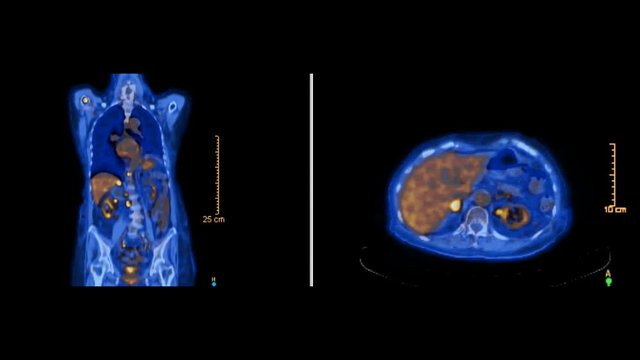

PET CT or Positron Emission Tomography  of whole human body for finding recurrent tumor. blue tone axial view pet scan. comparison coronal and axial view.

00:25